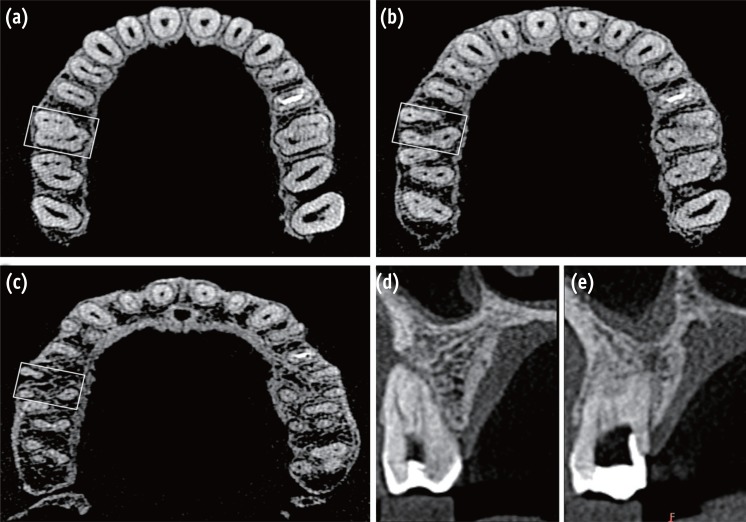

(a) A preoperative radiograph of teeth 16 and 17; (b - d) Working length radiographs of mesiobuccal (b), distobuccal (c), and palatal (d) roots of tooth 16 from distal, mesial, and straight angulations, respectively; (e - f) Master cone radiographs of mesiobuccal (e), distobuccal, and palatal roots (f) of tooth 16 from distal and mesial angulations, respectively; (g - h) Post-obturation radiographs of mesiobuccal (g), distobuccal, and palatal roots (h) of tooth 16 from distal and mesial angulations, respectively. MB, mesiobuccal; DB, distobuccal.

Even though initial visualization revealed additional canals present, however, several attempts to introduce a file into these orifices were unsuccessful. On further removal of dentinal shelf beginning from the orifice of the mesiobuccal and distobuccal canals and moving toward the orifice of the palatal canal with an ultrasonic micro-endodontic tip (ET 18D tip, Satelec Acteon, Merignac, France) clearly unveiled the orifice of additional canals. Negotiations of the canals were carried out with ISO size 06, 08, and 10 C-Pilot file (VDW GmbH, Munich, Germany) with clockwise and counter-clockwise rotational movement with apical pressure until the apex locator (Raypex5, VDW GmbH) reported that the apical patency was achieved. A glide path was established using size 15/0.01, 15/0.02 and 20/0.02 Hyflex Glide Path Files (Coltene-Whaledent) respectively. Coronal flaring was carried out using a NiTi size 25/0.08 Hyflex CM rotary instrument (Coltene-Whaledent) to improve the straight-line access. The working length which was initially determined with the help of an apex locator was later confirmed using individual radiographs for the mesiobuccal (Figure 1b), distobuccal (Figure 1c), and palatal root (Figure 1d) taken at different horizontal angulations. The working length radiographs showed that in the mesiobuccal root the MB2 canal merged with the MB3 canal at the apical third and exited through one apical foramen, whereas the MB1 canal had a separate canal orifice and exiting foramen. In the distobuccal root, the DB2 and DB3 canals merged with the DB1 canal at the middle and apical third respectively to form a single canal that exited through one foramen. Following which, the access cavities of both the teeth were temporized with a sterile cotton pellet and Cavit G (3M ESPE).

To confirm this rare and unusual morphology, dental imaging of the tooth with the help of CBCT (Carestream CS 9300, Carestream Dental LLC, Atlanta, GA, USA) was planned. An informed consent was obtained from the patient, and multi-slice scans of the maxilla was performed with a tube voltage of 90 KV and a tube current of 15 mA. All measures were taken to protect the patient from radiation. The involved tooth was focused, and the cross-sectional images were obtained in axial, transverse and sagittal planes (Figures 3a - 3e). All images were analyzed with the help of CS 3D imaging software (Carestream Dental LLC). Axial images were obtained at 180 µm thickness and were studied at cervical, middle and apical third of the roots to determine the canal morphology (Figures 3a - 3c). The images revealed that the tooth 16 had three roots and seven root canals (three mesiobuccal, three distobuccal, and one palatal). Transverse section CBCT scanned images of the mesiobuccal and distobuccal root confirmed the canal configurations that were seen in the working length radiographs (Figures 3d and 3e). In contrast, the contralateral tooth appeared to have a normal root canal anatomy (Figures 3a - 3e).

At the second appointment, the patient was asymptomatic. The tooth was anesthetized followed by rubber dam isolation. Cleaning and shaping was done using Hyflex CM rotary instruments along with lubricant (Glyde File Prep, Dentsply Maillefer, Tulsa, OK, USA) using the crown-down technique. All the mesiobuccal and distobuccal canals were enlarged to size 25/0.04, whereas the palatal canal was enlarged to size 40/0.04. Irrigation was performed using 3% sodium hypochlorite solution (Cmident, New Delhi, India) and 17% EDTA solution (Prevest Denpro Ltd, Jammu, India). The canals were finally flushed with sterile saline. Master cones were selected by placing gutta-percha cones (Dentsply Maillefer) corresponding with the size and taper of the last file used to the working length and was confirmed radiographically (Figures 1e and 1f). The canals were dried with absorbent points (Dentsply Maillefer), and obturation was performed using cold lateral compaction of gutta-percha and AH Plus resin sealer (Dentsply Maillefer). The tooth was then restored with a posterior composite resin core (P60, 3M ESPE). Final radiographs were taken to establish the quality of the obturation (Figures 1g and 1h). Tooth 17 was simultaneously treated using the same protocol as done for tooth 16. The patient remained asymptomatic during the 2 months of follow-up period.